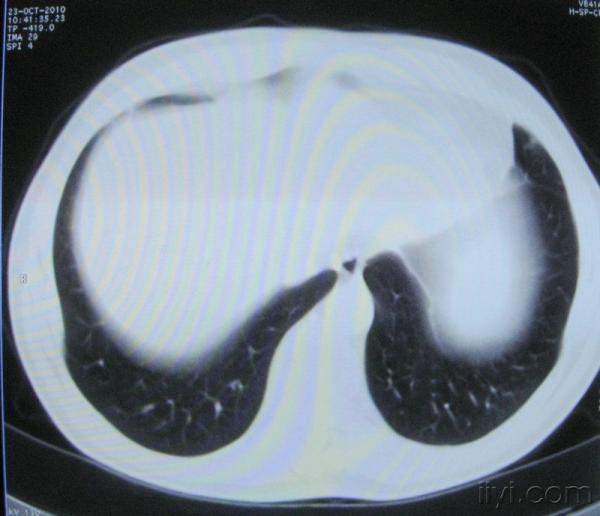

男。60岁,胸片示支气管炎治疗后复查CT。

你指那个肯定是淋巴结,中央系坏死,这很常见,特别在双侧腹股沟会经常看到。这个双侧腋窝及纵隔见多发小淋巴结征。

根据位置考虑应该是淋巴结,密度不均,是因为肿大的淋巴结中心液化坏死